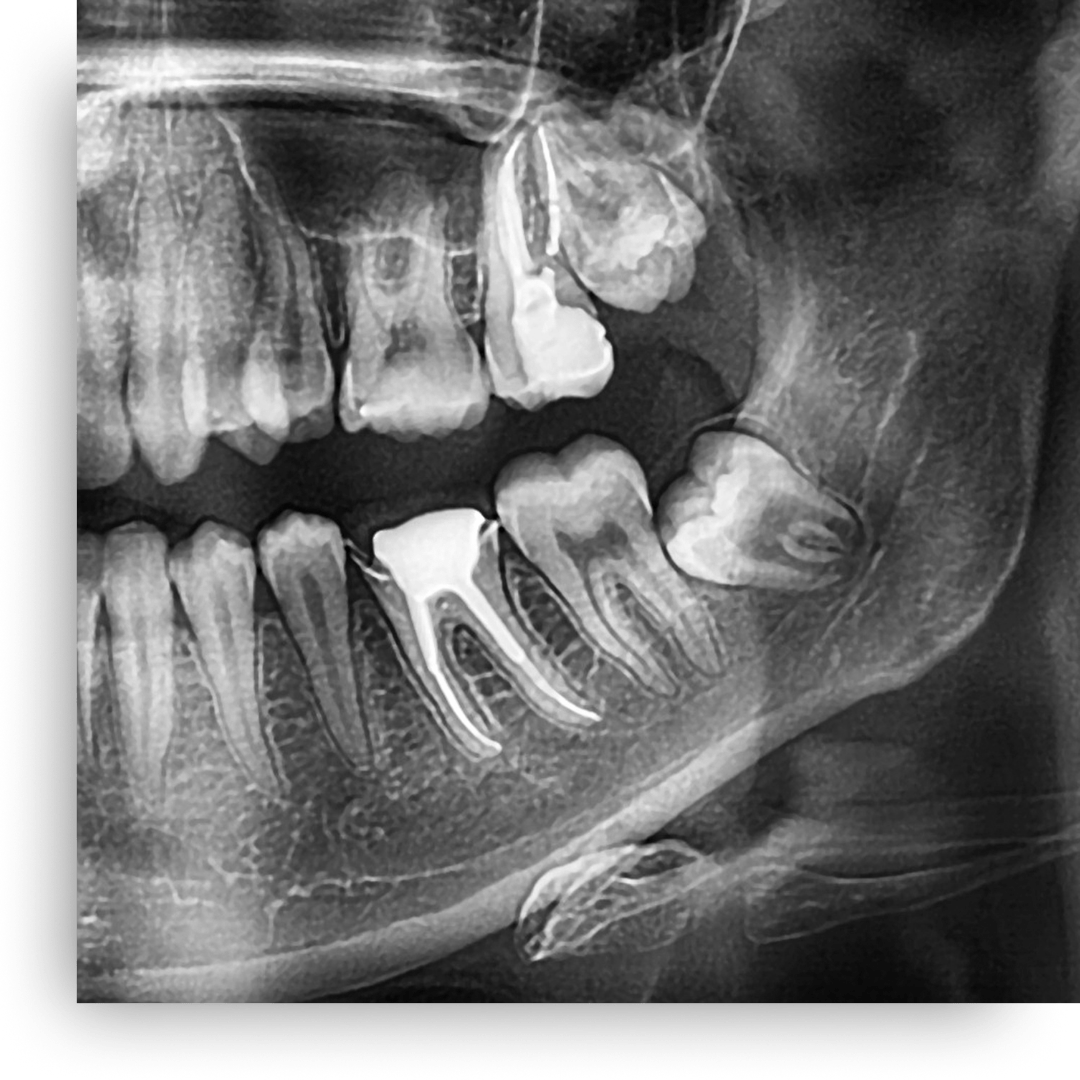

Wisdom teeth, or third molars, often cause problems as they erupt. They can become impacted (stuck), grow in at an angle, or crowd existing teeth. This can lead to pain, infection, and damage to adjacent teeth, making timely extraction a crucial preventive measure.

Our team prioritizes your comfort during the entire wisdom teeth removal process. We use modern techniques and sedation options to ensure a smooth, pain-free experience. We will clearly explain the procedure, from the initial X-rays to the extraction itself, so you feel confident and informed.